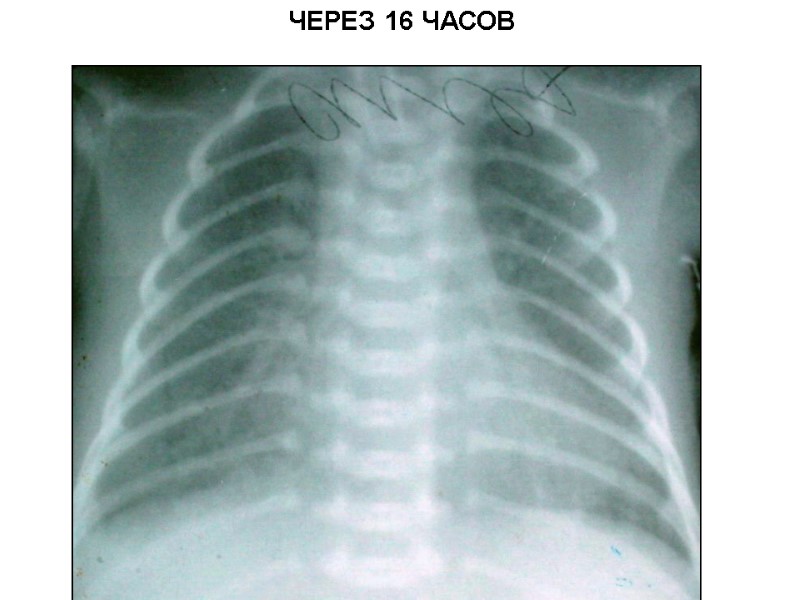

РДС-III. МОМЕНТ ВВЕДЕНИЯ КУРОСУРФА

ЧЕРЕЗ 16 ЧАСОВ